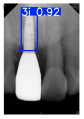

However, since the implant launched onto the market, dental treatment related to implant issues has become the everyday practice of dentists’ lives in clinics [10]. The design of the implants, from shape to surface coating, is different from brand to brand [11]. But it is inevitable to come into implant complications [12,13], such as screw fracture, healing abutment loss, etc., whether the clinician itself treats the implant or implant prosthesis. Different surface coatings [14,15] and threads of the implant design [16,17] may be easily identified in vitro. Moreover, once the implants are in vivo, the clinicians can only identify implant brands through radiography or the clinicians’ familiarity with the implant. If the clinicians are not familiar with the brands, then it is hard to tell which brand the implant is from in vivo. As the number of implant brands on the global market grows, it has become increasingly complex for clinicians to identify and familiarize themselves with all available implant systems accurately. 3i and Xive are two of the most widely used and clinically validated implant brands worldwide, with excellent long-term success rates [18] and reliable implant-abutment connection designs [19]. Therefore, we strategically focused on 3i and Xive implants in this study to ensure clinical relevance and practical significance. Concentrating on these two brands allows our model to address many real-world clinical cases and enhances its applicability in everyday dental practice. Clinicians will likely encounter both implant brands due to their widespread use in global dental clinics [20]. Moreover, as the implant’s screwdrivers differ from brand to brand, the identification of implant brands is very important to clinicians and patients. The marginal accuracy of the implant-abutment connection may vary due to misidentification and lead to unknown clinical problems [21,22]. The PA imaging results of two implant brands of different types at different resolutions (R) are shown in Figure 1. These two commonly used implant brands exhibit highly similar characteristics, with the most apparent difference being the variation in implant threading patterns. However, this distinction is not easily discernible for PA datasets.

Figure 1.

Imaging of two implant brands at different resolutions.